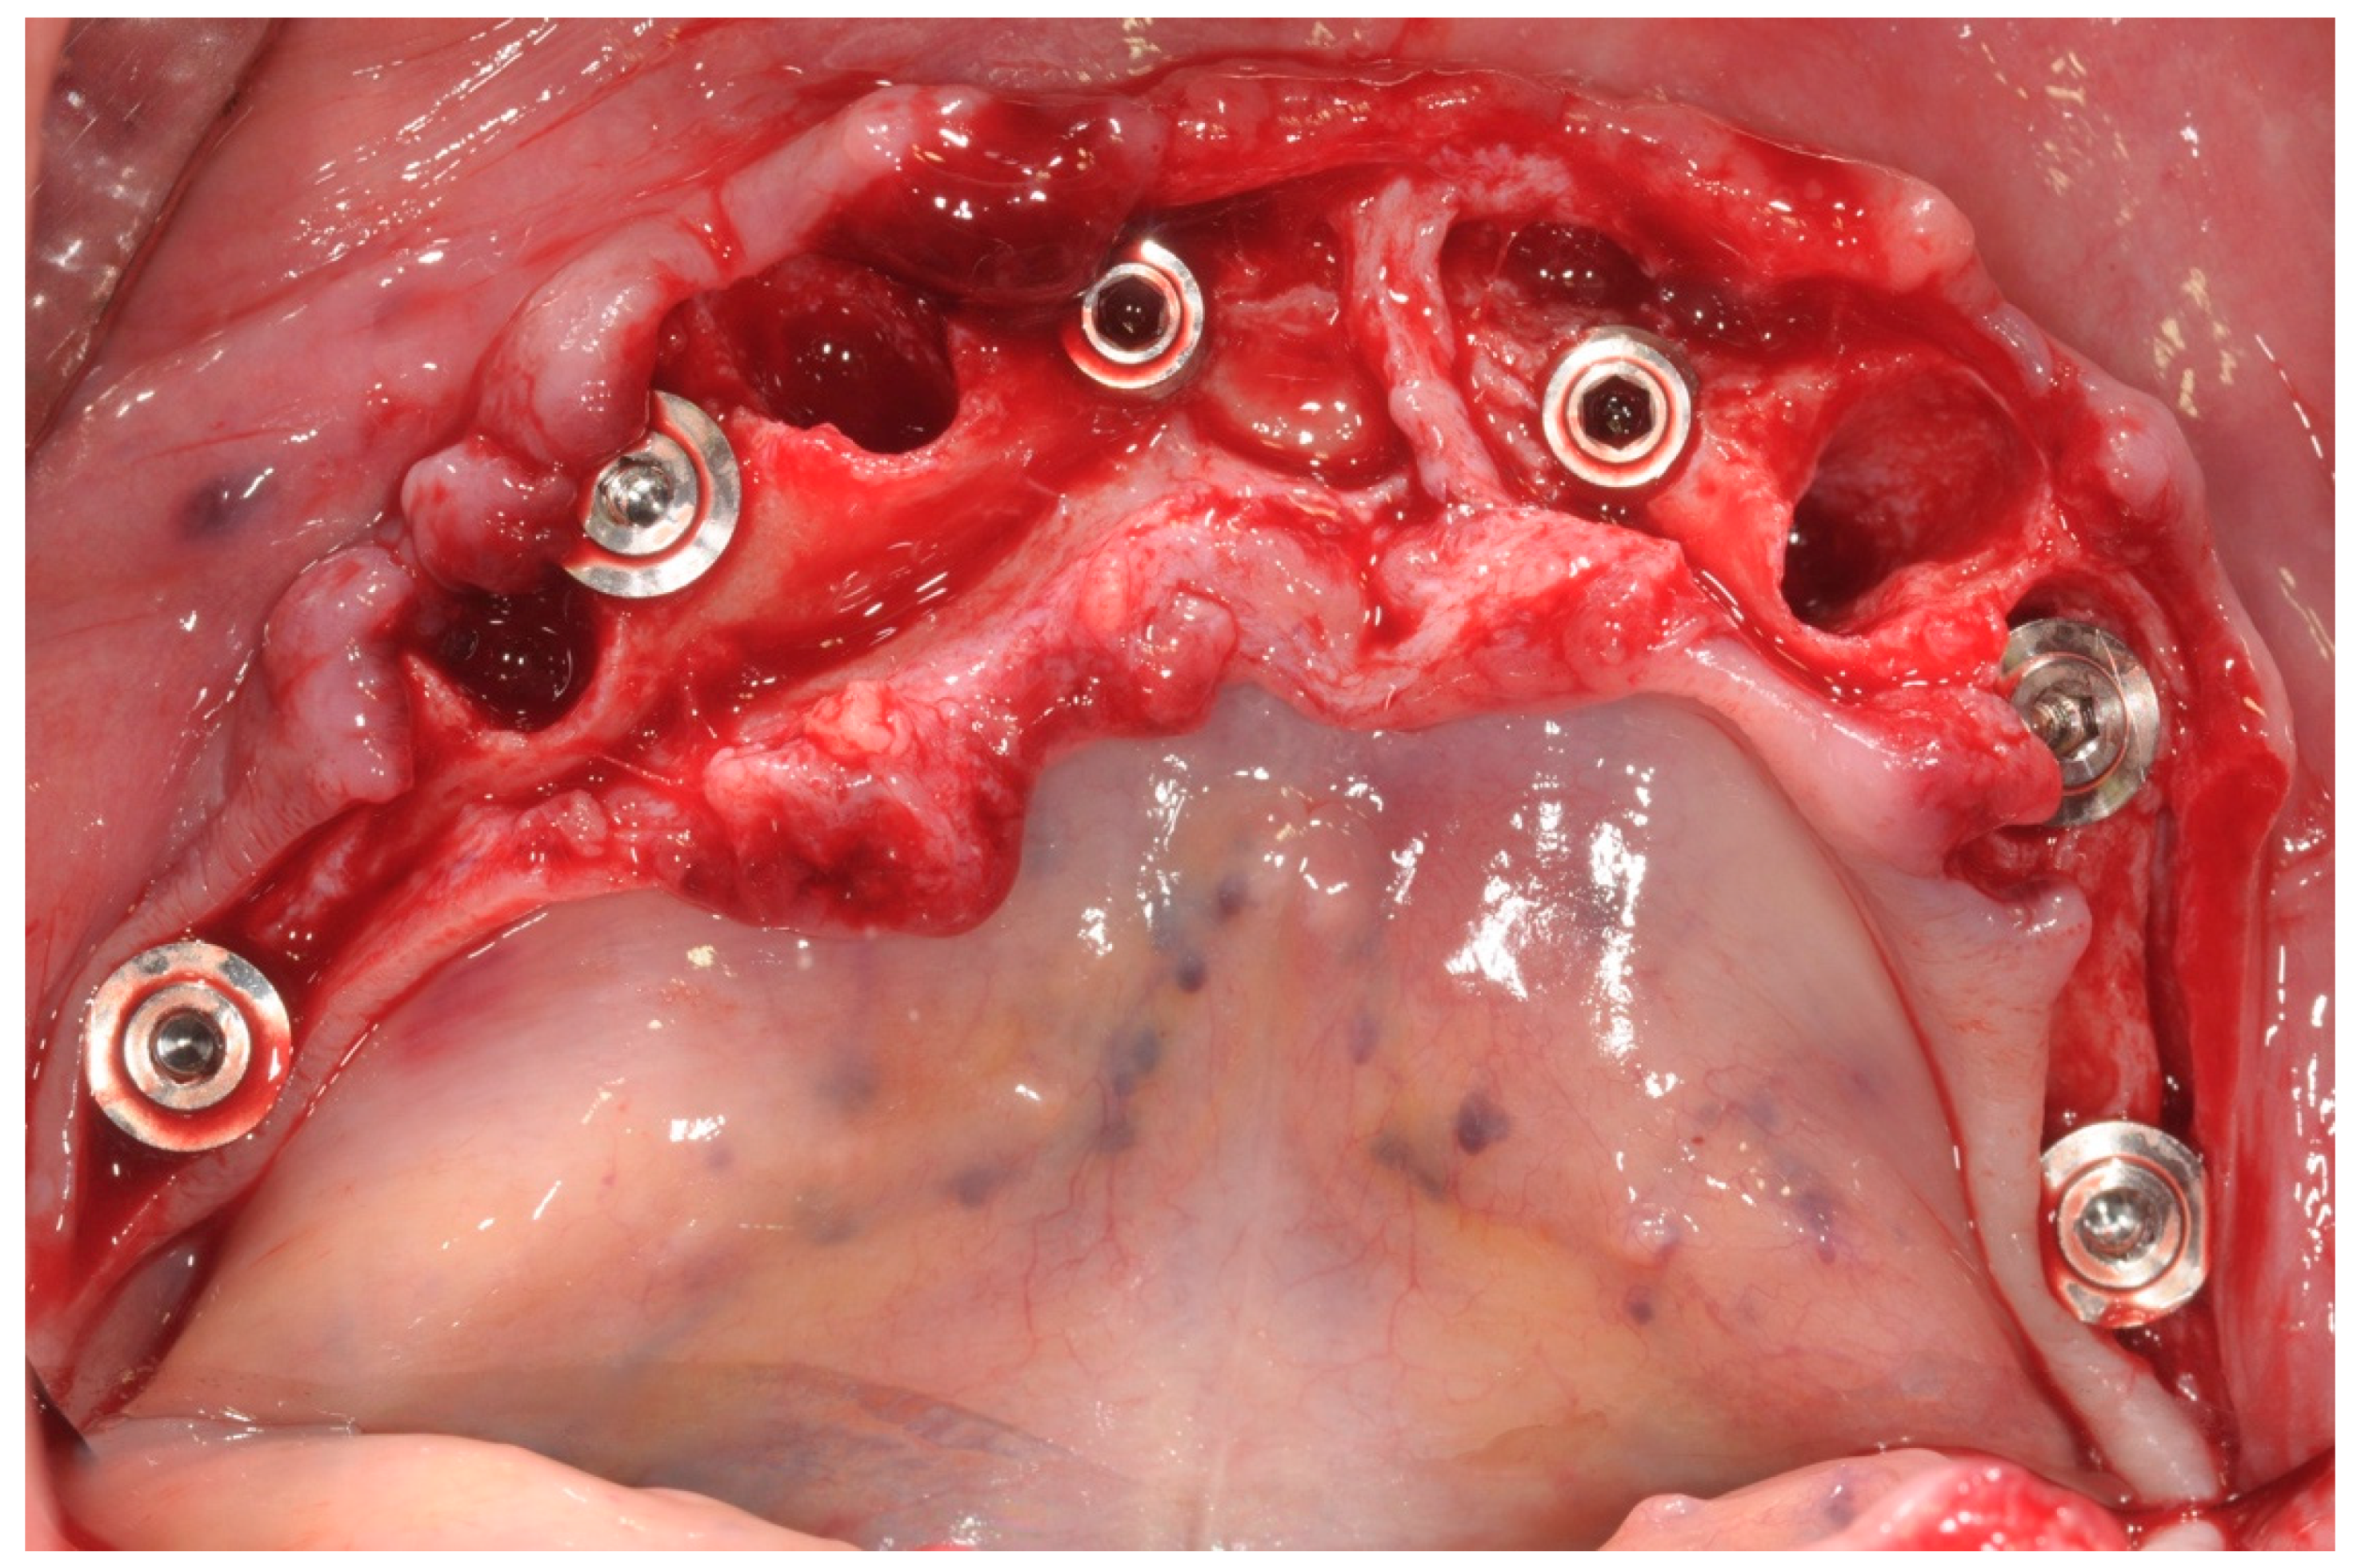

All patients were treated under local anesthesia, and patients received four, five, or six implants in the mandible according to the prosthetic treatment plan. In the case of tooth extraction sites, a periodontal probe was used to assess the integrity of the extraction socket’s bony walls and of the adjacent bone peaks to evaluate the feasibility of an immediate implant (Figure 2).

All patients received implants with a grit-blasted and acid-etched surface (Ossean®; Intra-Lock International®, Inc., Boca Raton, FL, USA) that were placed using a sterile surgical technique, as recommended by the manufacturer. Maximum care was taken to place the implants, regardless of whether they were inserted in an edentulous ridge or an extraction site, with a minimum insertion torque of 35 Ncm and not exceeding 50 Ncm (Figure 3).

The peri-implant bone defects in the extraction sockets were grafted with a cortico-cancellous porcine bone (GTO, Tecnoss-Dental, Giaveno, Italy). Flat abutments (FlatOne®; Intra-Lock International®, Inc., Boca Raton, FL, USA) were then connected to the implants, and the flap was sutured (Figure 4).

Figure 2. Operative site after tooth extractions.